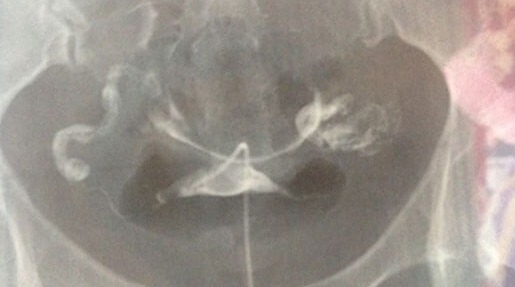

自然周期中,女性通常仅单侧卵巢排出一个成熟卵泡,且排卵时间集中在月经周期第14天左右。若双侧卵巢同步排卵(即两侧卵巢在相近时间内各排出一个卵子),且两个卵子均与精子结合,则可能形成异卵双胞胎。但自然状态下双侧同步排卵的概率不足5%,更多见于促排卵药物干预或遗传性排卵特征人群(如家族有双胞胎史者)。例如,使用克罗米芬等促排卵药物后,多卵泡发育概率可提升至20%-30%,显著增加双胎妊娠风险。

受精卵需成功植入子宫内膜才能发育为胎儿。子宫环境异常(如内膜过薄<7mm、宫腔粘连、子宫肌瘤)会显著降低着床率。即使两个受精卵均到达子宫,若内膜容受性差,可能仅一个胚胎存活,或均因缺氧、营养不足而停止发育。研究显示,子宫内膜厚度在8-12mm时,双胎妊娠成功率最高,且需激素水平(如雌激素>200pg/mL、孕酮<1.5ng/mL)与胚胎发育同步。